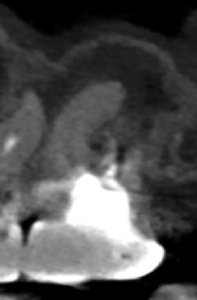

複数根管があるのはMBであるが、

これらの絵だけで合流しているか?否か?がわかるだろうか?

またMB2は見つかるだろうか?

その際は、

この辺りを探索する必要があるだろう。

短針でスカウティングする際に、掴めるポイントは全て突いた方がいいだろう。

どこが本当のMB2の入口か?判別できないからだ。

またMB2の多くはMB1と合流するという臨床的事実から形成済みのMB1に当該Gutta Percha Pointを挿入しMB2にFileを入れてグリグリとやってみた。

すると…

13.5mmの地点に傷がついていることがわかる。

ここが合流地点だろう。

これで以下のように作業を行った。

MB2は狭窄根管だがMB1と合流しているので13.5mmとして形成した。